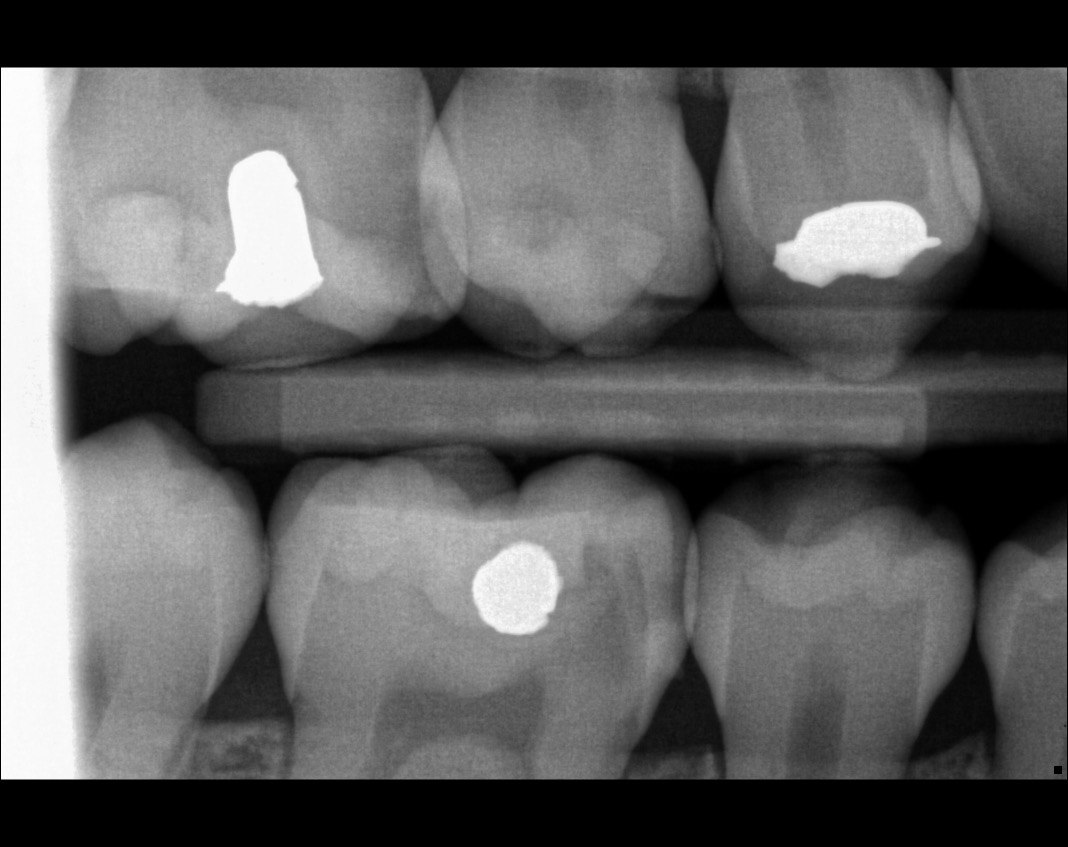

31. What option cannot be selected for the tooth # 3.6?

32. What options cannot be seen in the print of this X ray?

33. What options cannot be seen in the print of this X ray?

34. What option can be selected for tooth # 4.6?

35. What options cannot be selected for the tooth # 1.5?

36. What options cannot be selected for the tooth # 3.7?

37. What options can be selected for tooth # 1.2?

38. What option can be seen in the print of this X ray?

39. What options can be selected for the print of this X ray?

40. What cannot be seen in the print of this X ray?